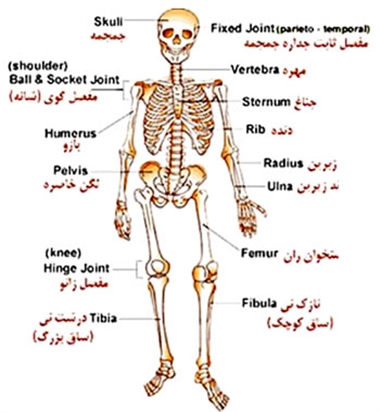

عکس اسکلت بدن انسان با کیفیت. عکس اسکلت عکس اسکلت برای پروفایل عکس اسکلت انسان عکس اسکلت خفن عکس اسکلت بدن انسان با کیفیت عکس اسکلت بدن انسان عکس اسکلت ترسناک عکس اسکلت فانتزی عکس اسکلت فانتزی دخترانه پرچم عکس اسکلت. عکس با کیفیت اسکلت داخلی انسان و درد و گرفتگی در ناحیه استخوان زانو ویژه استفاده در امور تبلیغاتی و تجاری طراحی کاتالوگ بروشور و تراکت با موضوع پزشکی فیزیوتراپی ارتوپد دکتر روماتیسم فیریوتراپ طب فیزیکی. عکس اسکلت بدن انسان زن و مرد آناتومی ساتین 16 سپتامبر 2017. اسکلت داربست بدن است تمام قسمت های بدن روی اسکلت قرارگرفته اند بدن انسان از ۲۰۶ قطعه استخوان تشکیل شده است این استخوان ها طوری با نظم کنار هم قرار گرفته اند که انسان را قادر می سازد حرکات دقیقی داشته باشد.

اسکلت جمجمه و گردن انسان ستون فقرات آناتومی اسکلت جمجمه و گردن انسان ستون فقرات آناتومی تصویر با کیفیت را از لینک زیر می توانید دانلود کنید. ۱ مطلب با کلمه ی کلیدی عکس اسکلت بدن انسان با کیفیت ثبت شده است گالری نسیم جدید ترین و با کیفیت ترین عکس های مناسبتی. عکس با کیفیت آناتومی اسکلت بدن انسان و درد و دیسک در قسمت مهره های ستون فقرات کمر ویژه استفاده در امور تبلیغاتی و تجاری طراحی کاتالوگ بروشور و تراکت با موضوع بیمارستان ها و کلینیک ها و درمانگاه ها و مطب ها پزشکان و.